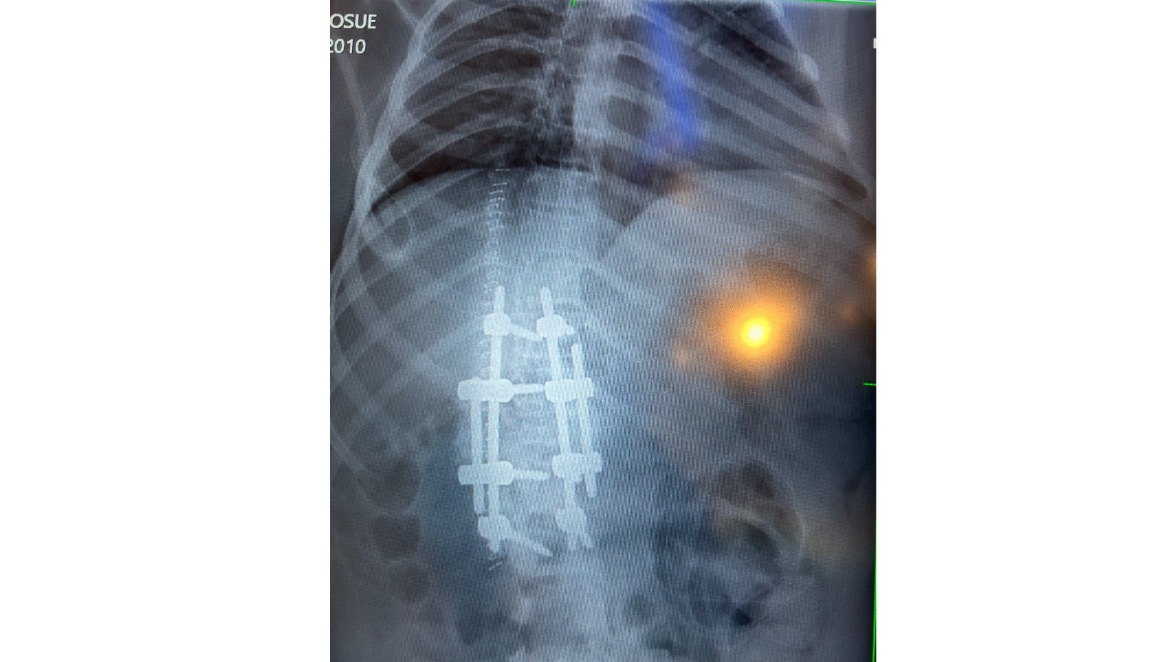

Now a bilateral (double) below-the-knee amputee, on December 10, 2025 Josue also underwent a major spinal fusion surgery to stabilize his back. While the surgery was necessary, he emerged in a delicate and terrifying state. He suffered a severe systemic allergic reaction, with hives covering his entire body. His condition became so critical that he required a blood transfusion and was placed in the ICU.